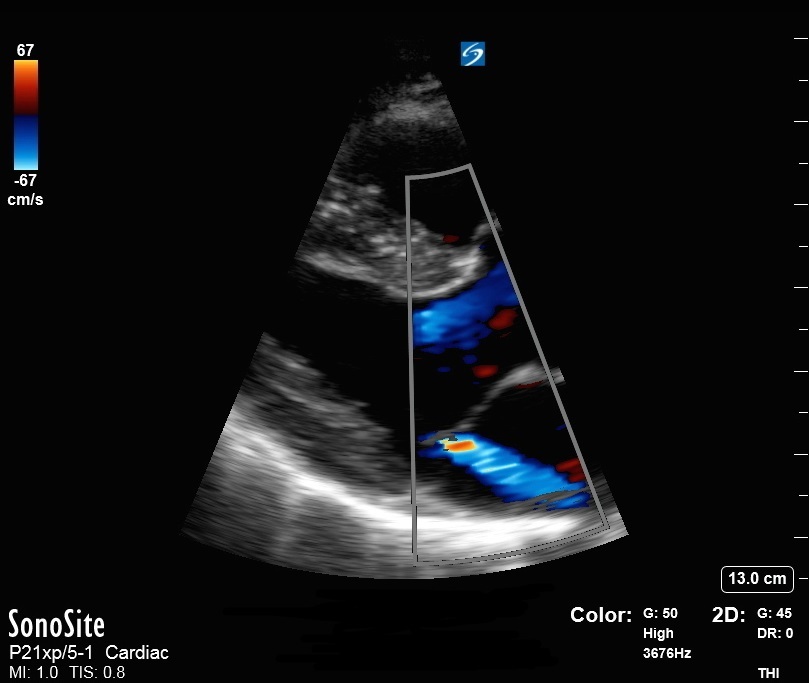

心脏胸骨旁长轴 (PLAX) 二尖瓣反流图像